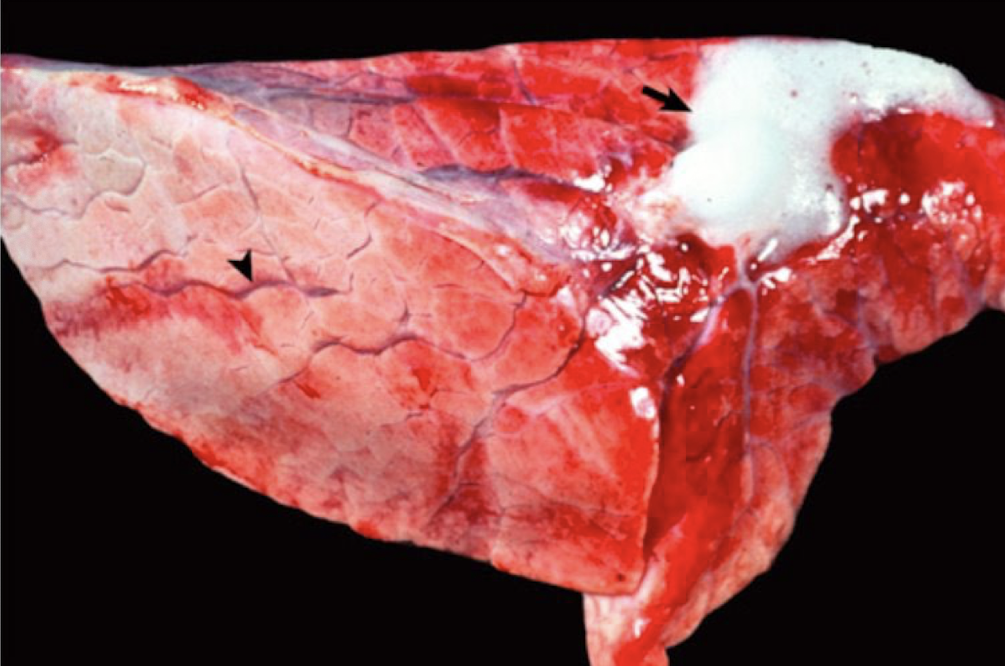

<p>What is this showing?</p>

What is this showing?

persistent right aortic arch (PRAA)